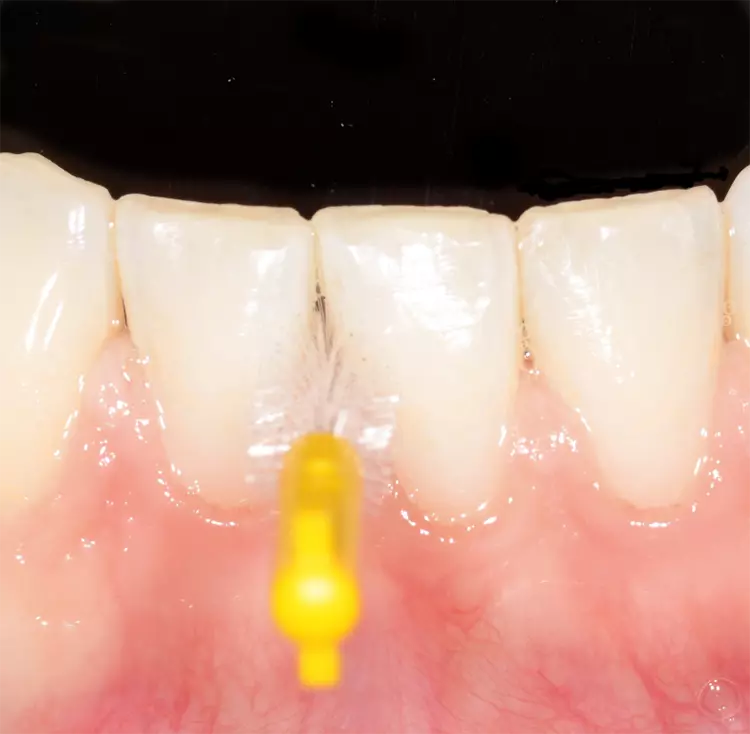

Man benötigt gerade in solchen Situationen ein ausreichendes Sortiment größerer Interdentalraumbürsten, wenn man das Ziel verfolgt, bei der Anwendung den jeweiligen Taschenfundus zuverlässig zu erreichen (Abb. 5).

Sowohl in der initialen Behandlungsphase nach Erstdiagnose einer Parodontitis als auch im Rahmen der Erhaltungstherapie (unterstützende Parodontitistherapie/UPT) besitzt die individuelle Mundhygieneschulung mit regelmäßiger Anpassung von Interdentalraumbürsten eine hohe Relevanz. Die Empfehlung der korrekten und passgenauen Interdentalraumbürste wird allerdings u. a. durch eine zu geringe Auswahl von Produkten mit größerer Reichweite erschwert.